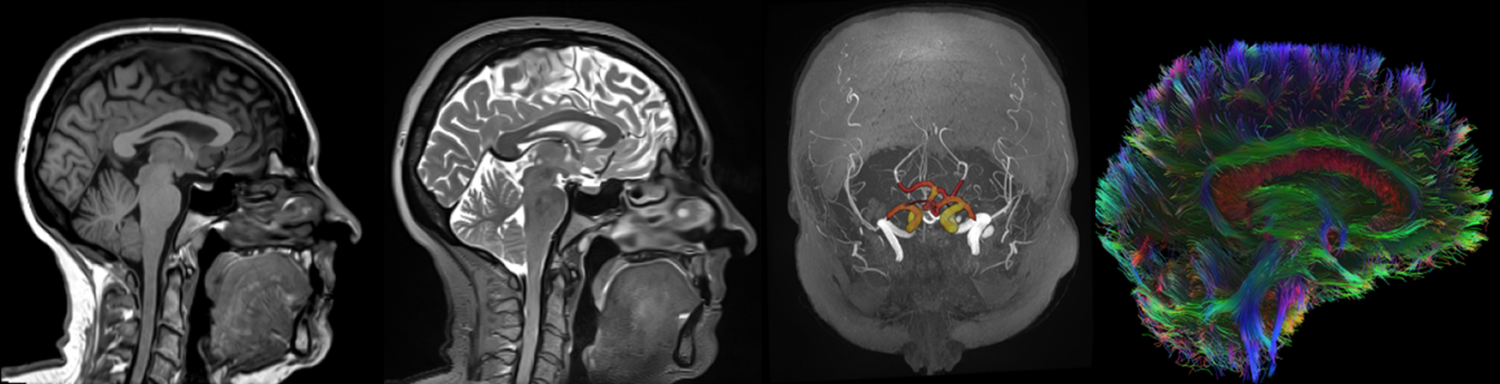

Den nye skanneren kommer til å forbedre muligheter for MR i forskning og undervisning ved UNN og UiT, gjennom økt kapasitet og ny teknologi. Kapasiteten vil være på 1500 – 2000 undersøkelser i året. Ny banebrytende teknologi vil gi bedre bildekvalitet, hurtigere undersøkelser og muliggjøre bruk av nye teknikker.